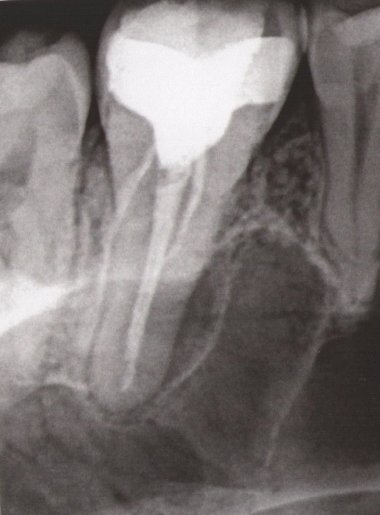

Уважаемая Мария, этот снимок немного не информативный, множество наложений и теней. Я вам рекомендую приехать на очный прием и я вам все подробно расскажу.